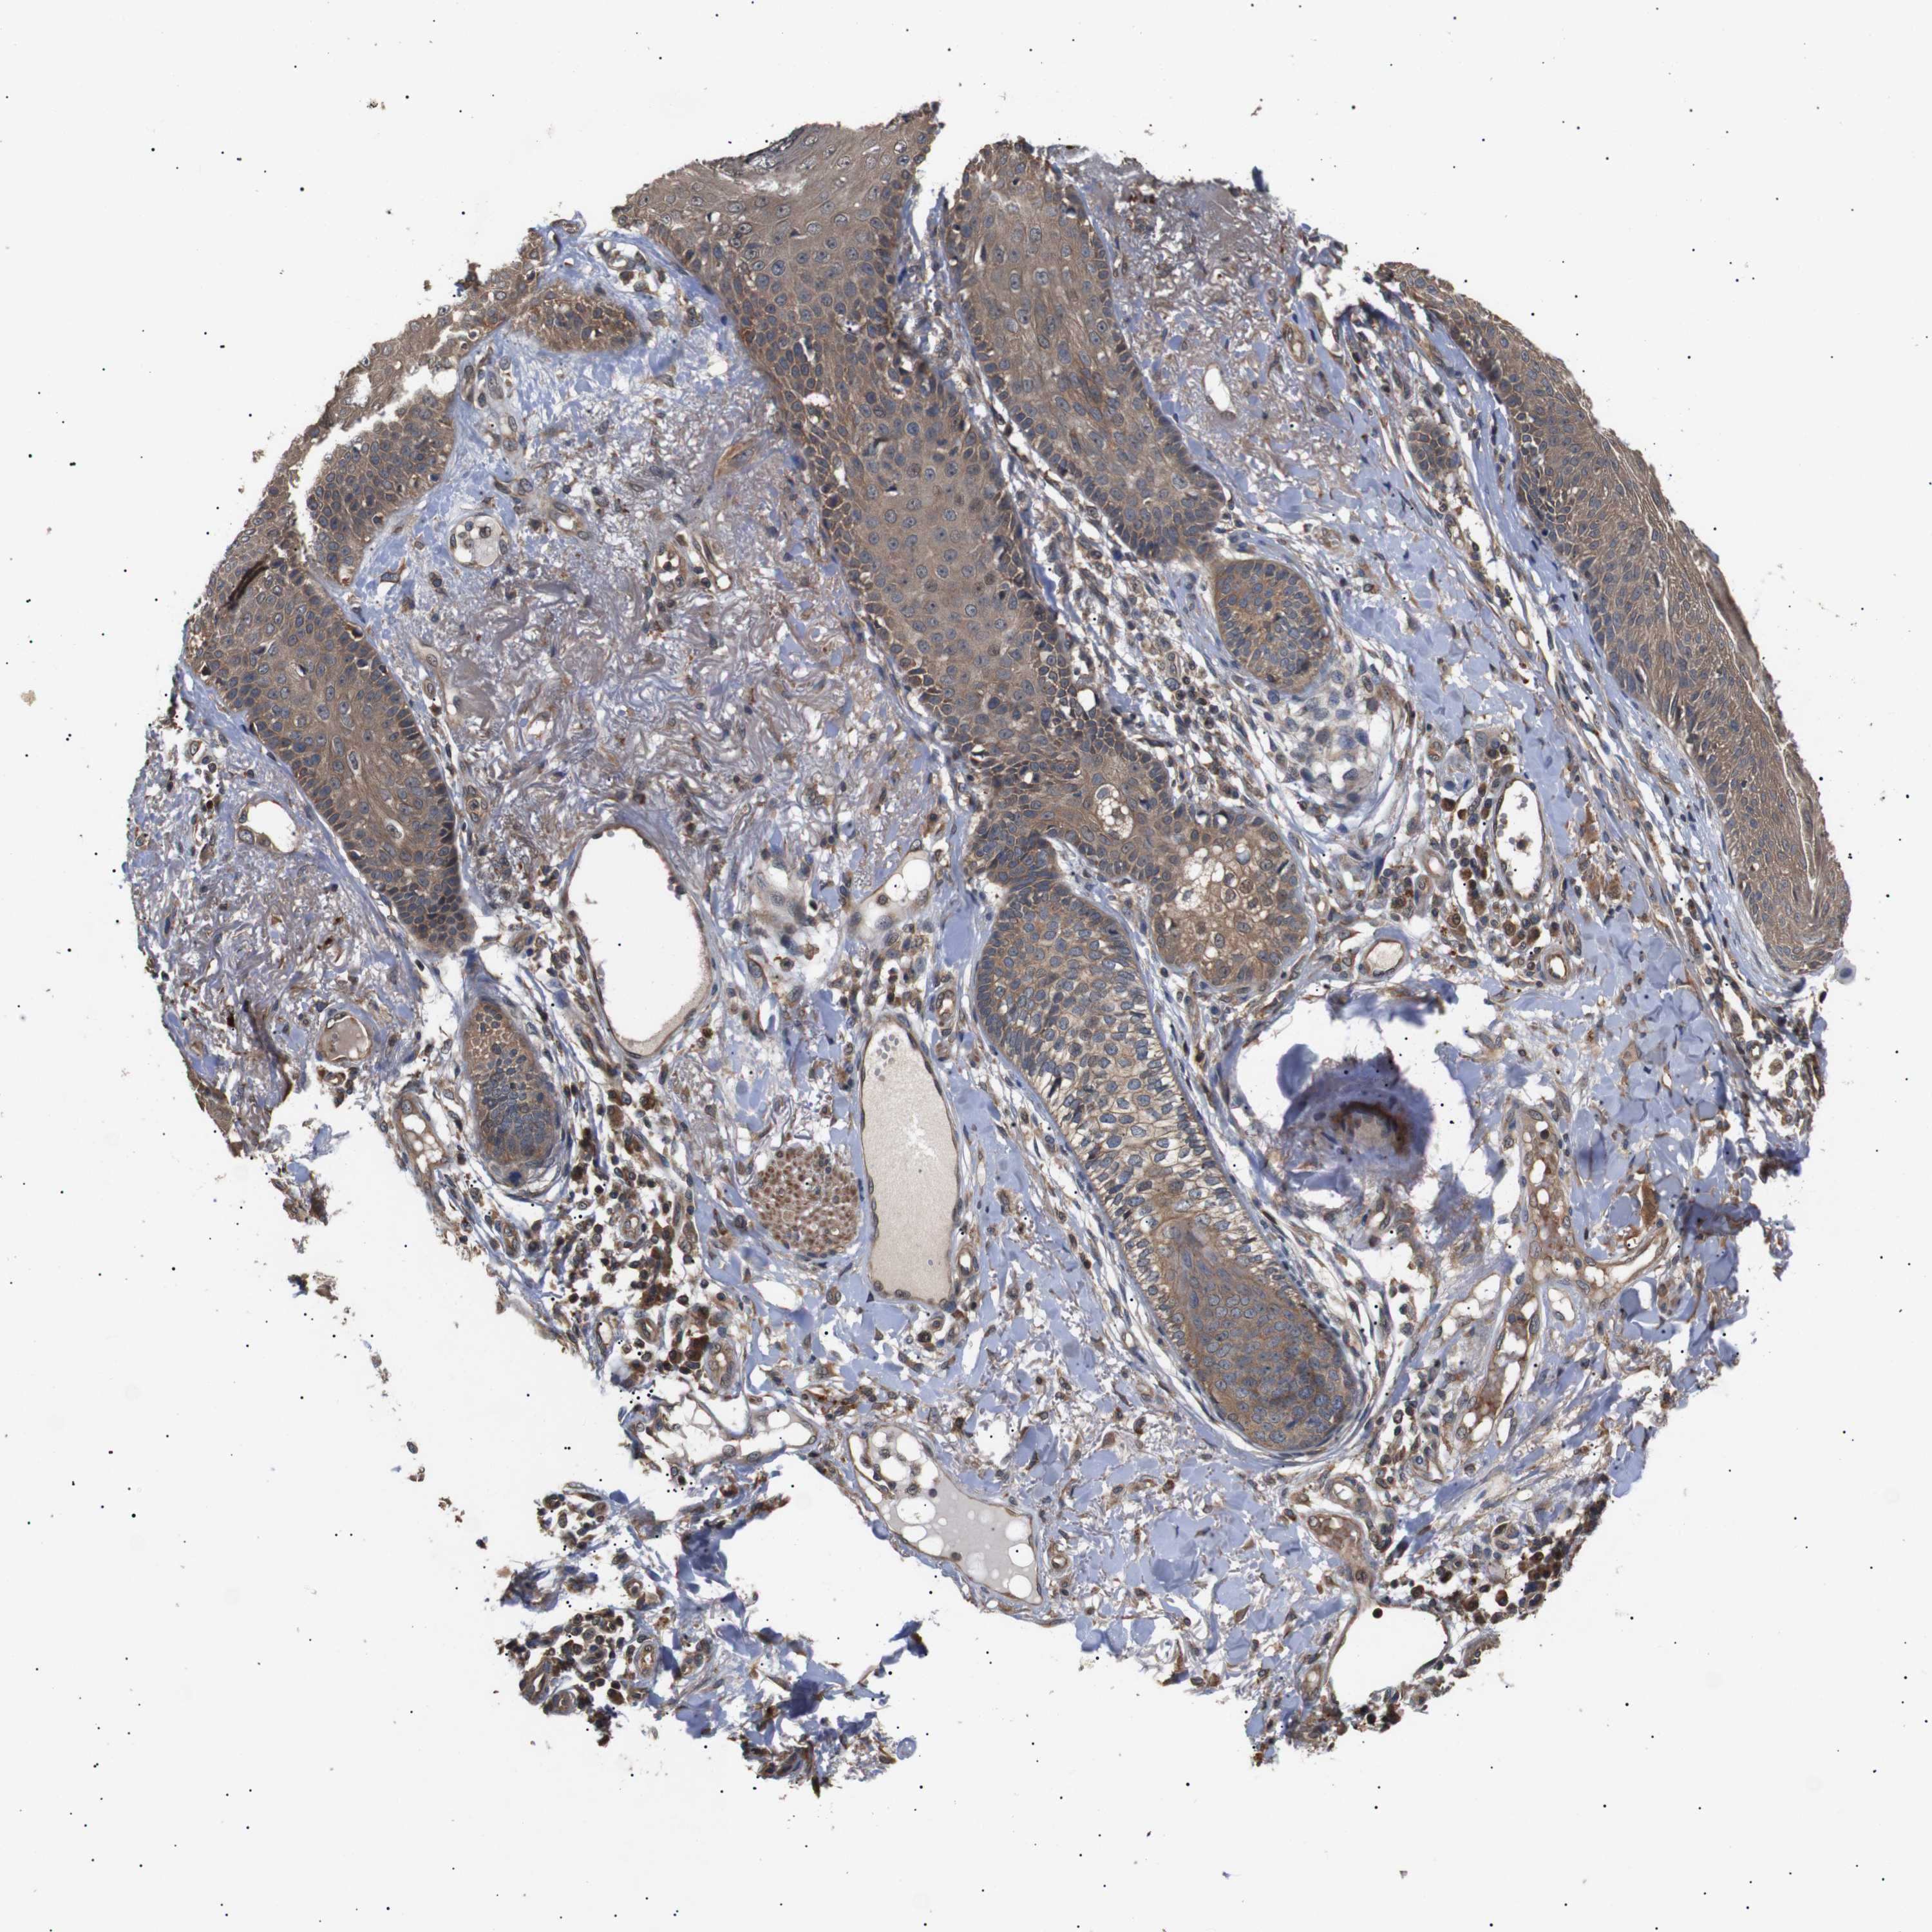

SKIN CANCER - Protein expressioni

A mouse-over function shows sample information and annotation data. Click on an image to view it in a full screen mode. Samples can be filtered based on level of antibody staining by selecting one or several of the following categories: high, medium, low and not detected. The assay and annotation is described here.

Antibody staining in the annotated cell types in the current human tissue is reported as not detected, low, medium, or high, based on conventional immunohistochemistry profiling in selected tissues. This score is based on the combination of the staining intensity and fraction of stained cells.

Each image is clickable and will lead to virtual microscopy that enables deeper exploration of all samples and also displays staining intensity scores, fraction scores and subcellular localization as well as patient and tissue information for each sample.

Antibody CAB025656

Staining

Low

Squamous cell carcinoma, NOS

Squamous cell carcinoma, metastatic, NOS